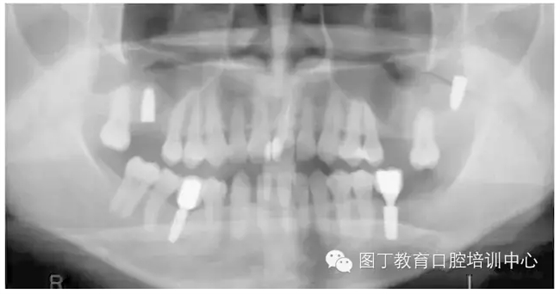

病例8 多顆種植體植入(圖10)

圖10